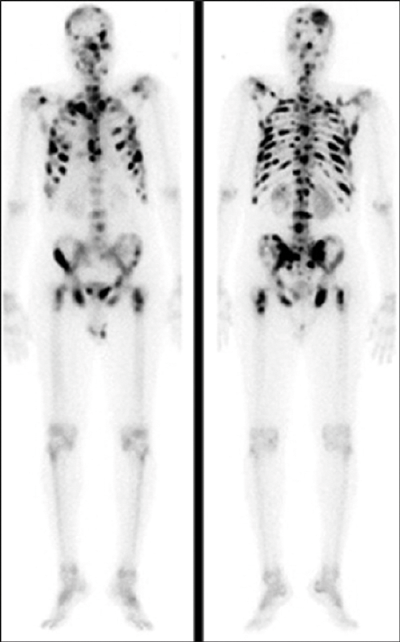

A 74-year-old gentleman is referred with a PSA of 238ng/ml. DRE reveals a hard nodular prostate.

- What type of radiological imaging is shown?

- What is the radiation exposure of this scan?

- What does it demonstrate?

This is a bone scintigraphy or radionuclide whole body isotope bone scan.

Radiation exposure: 4-6 mSV.

The bone scan demonstrates ‘superscan’ due to extensive osteoblastic metastasis. When there is diffuse metastasis, all of the radiotracer is concentrated in the skeleton with little or no activity in the soft tissues or urinary tract.